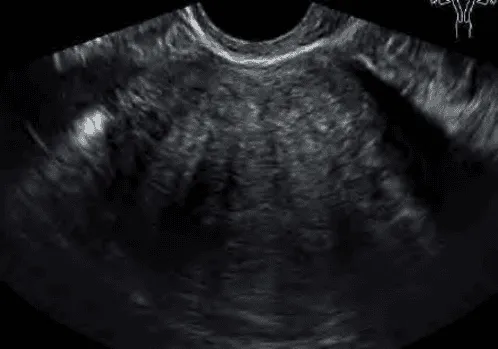

Hình ảnh “Adenomyosis trên siêu âm”.